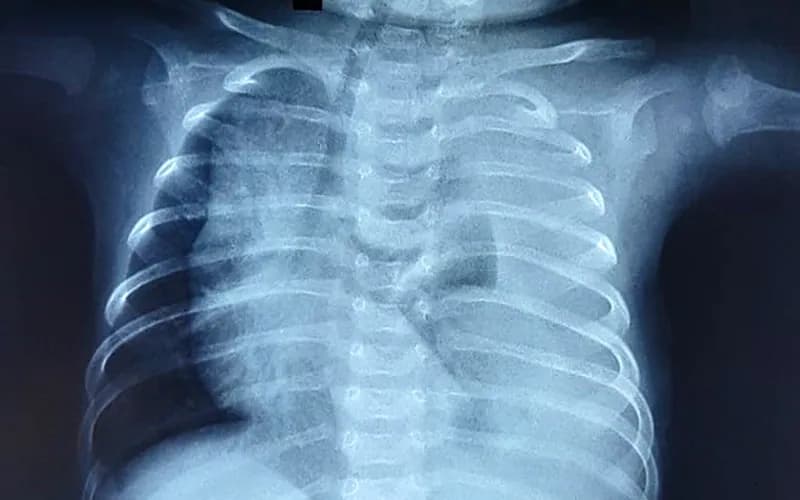

2.8. X-quang phổi

- Vai trò:

- X-quang phổi là một công cụ hữu ích trong việc phân biệt giữa các rối loạn tim và phổi. Việc kiểm tra các trường phổi giúp xác định các nguyên nhân phổi chính gây tím tái, bao gồm tràn khí màng phổi, giảm sản phổi, thoát vị cơ hoành, phù phổi, tràn dịch màng phổi hoặc bệnh đường thở.* Các đặc điểm gợi ý tổn thương tim:

- Ba đặc điểm của phim X-quang ngực có thể gợi ý các tổn thương tim cụ thể là kích thước hoặc hình dạng tim, dấu hiệu mạch máu phổi và vị trí của cung động mạch chủ. * Kích thước hoặc hình dạng trái tim: * Kích thước tim: Bệnh nhân có tổn thương tắc nghẽn bên trái có thể bị tim to do suy tim. Tim cực to gợi ý các tổn thương liên quan đến tâm nhĩ phải giãn vì buồng này rất phù hợp. Chúng bao gồm teo động mạch phổi với vách liên thất còn nguyên vẹn hoặc bất thường Ebstein. * Hình dạng tim: Các bất thường đặc trưng của hình dạng tim có liên quan đến các tổn thương cụ thể: * TOF - Tim hình chiếc ủng (coeur en sabot). * D-TGA - Hình trứng trên một chuỗi gây ra bởi bóng trung thất hẹp tạo ra bởi mối quan hệ trước-sau chứ không phải trái của các động mạch lớn. * Dấu hiệu mạch máu phổi: Hình thái dòng máu phổi phụ thuộc vào tổn thương tim cụ thể. Mặc dù dấu hiệu mạch máu phổi giảm xảy ra ở hầu hết các tổn thương TBS tím, chúng tăng lên ở những bệnh nhân thân chung động mạch hoặc các tổn thương hỗn hợp, chẳng hạn như kênh nhĩ thất thông thường, do sức cản mạch máu phổi giảm sau khi sinh. * Trong D-TGA, các dấu mạch máu có thể không đối xứng. Trong tình trạng này, các nhánh động mạch phổi phải từ động mạch phổi chính dọc theo trục dài của tâm thất trái, trong khi các nhánh động mạch phổi trái theo chiều dọc. Giải phẫu này thường thúc đẩy tăng lưu lượng ưu tiên đến phổi phải và lưu lượng máu không đối xứng với giảm đánh dấu ở phổi trái. * Tình trạng tắc nghẽn tĩnh mạch phổi do suy tim được đặc trưng bởi các dấu mạch không rõ ràng lan rộng theo hình bướm từ vùng trung tâm của lồng ngực. Điều này thường thấy trong kết nối tĩnh mạch phổi bất thường toàn bộ bị tắc nghẽn hoặc suy tim do tổn thương tắc nghẽn bên trái (HLHS hoặc coarctation nặng của động mạch chủ) hoặc bệnh cơ tim. * Vị trí của cung động mạch chủ: Vị trí của cung động mạch chủ được xác định bởi phế quản gốc nào mà cung bắt chéo. Điều này được xác định tốt nhất bằng sự thụt vào của khí quản trên hình ảnh phía trước, cho thấy phía mà cung động mạch chủ đang uốn cong. Giải phẫu bình thường là cung động mạch chủ bên trái với sự thụt vào của khí quản bên trái khi cung bắt chéo qua phế quản thân trái. * Cung động mạch chủ bên phải dẫn đến một vết lõm ở bên phải của khí quản. Khoảng 20% bệnh nhân TOF và 30% bệnh nhân thân chung động mạch có cung động mạch chủ bên phải. Bởi vì TOF phổ biến hơn nhiều so với thân chung động mạch, một cung động mạch chủ bên phải ở trẻ sơ sinh tím thường gợi ý TOF. Cung động mạch chủ bên phải cũng có thể kết hợp với các tổn thương khác, chẳng hạn như chuyển vị của các động mạch lớn.